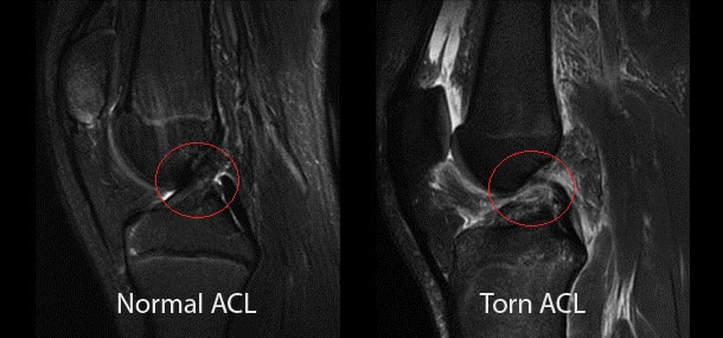

How is a meniscus injury diagnosed?

The orthopedic surgeons at MedStar Health are experts at diagnosing meniscal injuries. Our initial exam generally includes:

What tests are done to check for swelling in the knee?

- A torn meniscus often can be identified during a physical exam. Your doctor might move your knee and leg into different positions, watch you walk, and ask you to squat to help pinpoint the cause of your signs and symptoms.